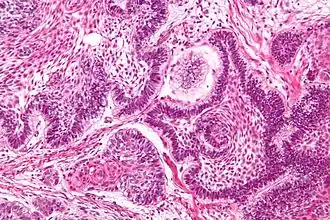

It is one of the components of koilocytosis, which may be present in potentially pre-cancerous cervical, oral and anal lesions.[2]